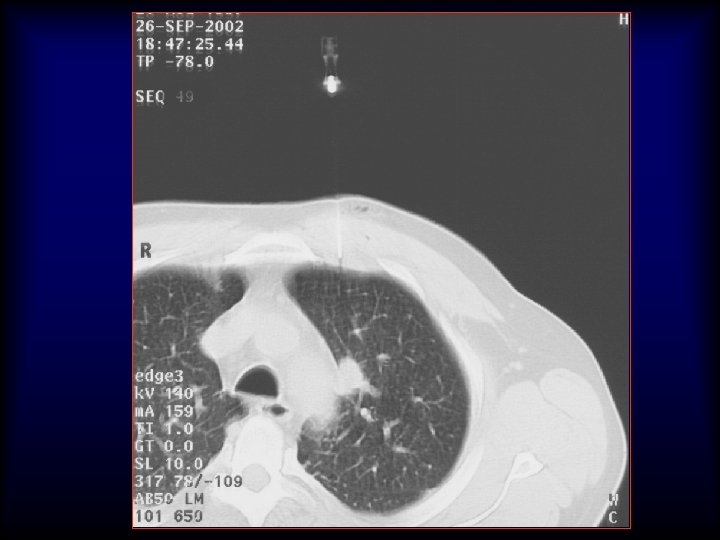

Advanced Lung analysis 1. Μεταβολή του μεγέθους (Volume) του όγκου Ø Γρήγορο doubling time

Advanced Lung analysis 1. Μεταβολή του μεγέθους (Volume) του όγκου Ø Γρήγορο doubling time Authors of a number of other series (20, 21) have confirmed similar findings and have estimated the median tumor doubling times, assuming a constant growth rate to be in the 160– 180 -day range.